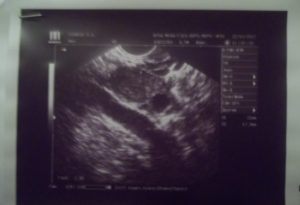

В это время плодное яйцо благодаря усиленному делению клеток достигает диаметра в 2 мм. Оно имеет форму небольшого шарика. После того как зародыш прочно прикрепился к внутренней полости матки, наблюдается полная блокировка менструаций. Начинает формироваться плацента, которая необходима для защиты малыша.

При ощущении некоторых изменений в организме, можно обратиться к врачу-гинекологу для назначения УЗИ. На таком сроке УЗИ уже способна подтвердить наличие плода внутри матки.

Внедрение в стенки живота сопровождается наличием незначительных кровянистых выделений и легкой тянущей боли, появляющейся внизу живота. Имплантация занимает примерно 40 часов, после этого УЗИ определяет наличие плода в матке. Она происходит за счет деления и вживания в слизистую оболочку внешних клеток зиготы.

Деление клеток на данный момент ускоренное. Вскоре происходит образование кровеносных сосудов, которые становятся плацентой. Именно благодаря плаценте плод будет получать из материнского организма все необходимые ему вещества аж до рождения.